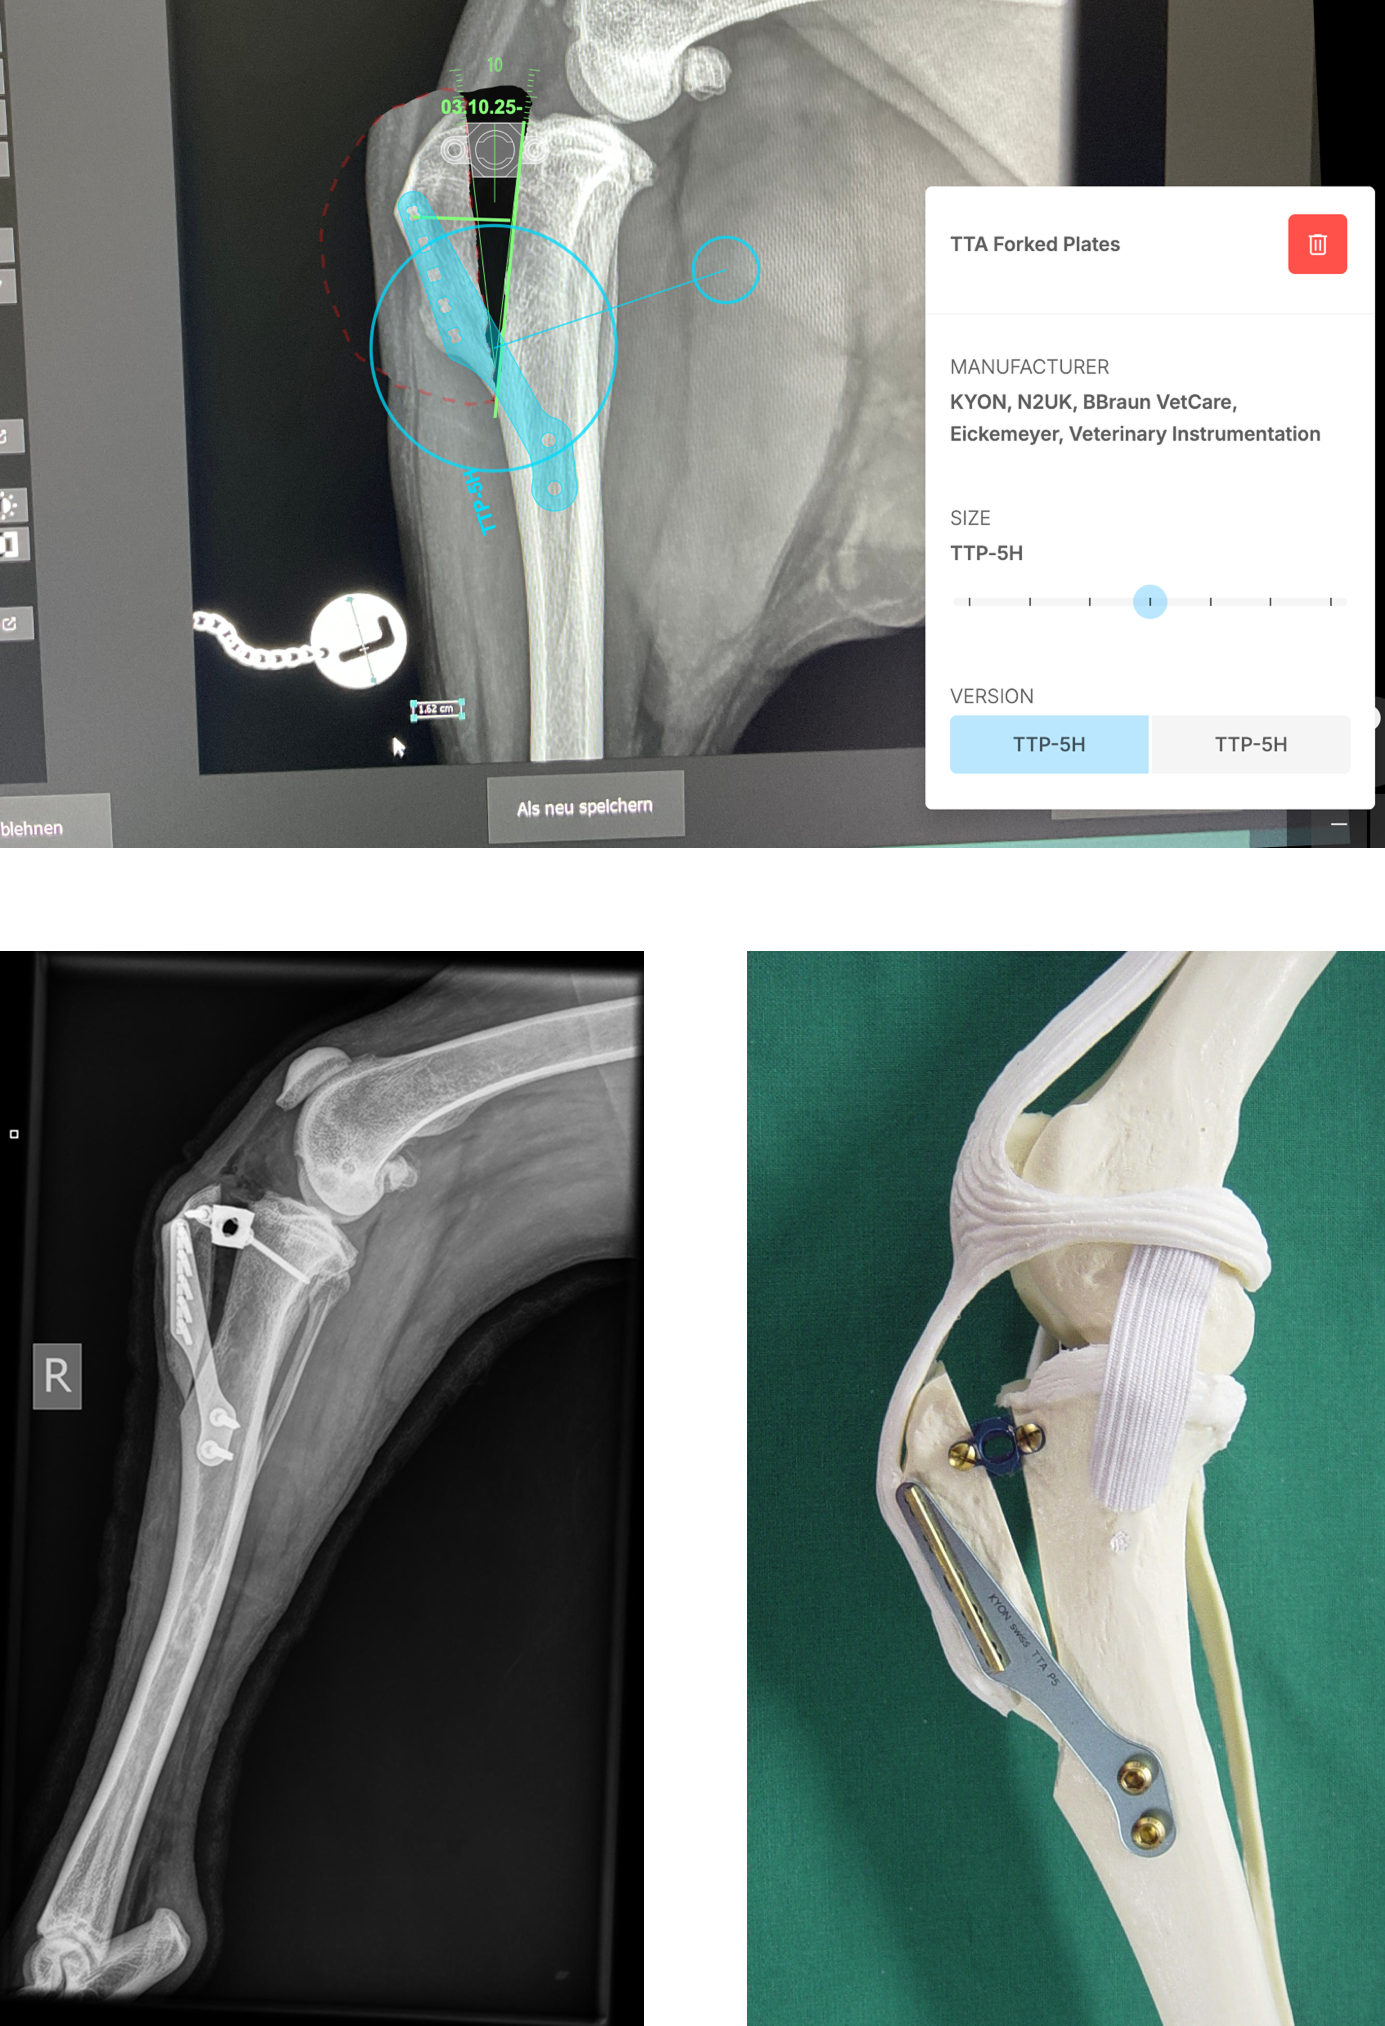

Bildmaterial

• Postoperative Röntgenaufnahme: zeigt die Tibia mit eingesetzter Platte und Schrauben nach einer TTA-Operation.

• Modell eines Kunststoffknochens: veranschaulicht die Position der Platte und des Abstandhalters an der proximalen Tibia.

• Präoperativer Plan am Computer: Beispiel einer digitalen Planung mit Auswahl der passenden Platte und Messung des Vorschubs.